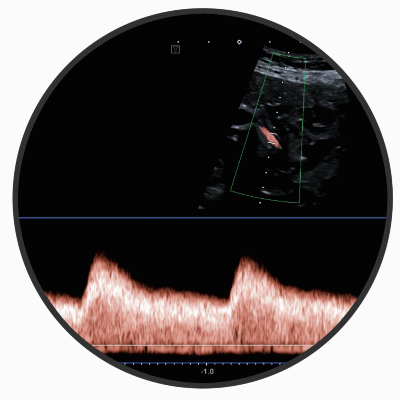

DOPPLERSONOGRAPHIE

In diesem speziellen Verfahren werden die Durchblutung des Mutterkuchens und die kindliche Blutversorgung überprüft. Zusätzlich wird dabei auch das Wachstum Ihres Kindes untersucht. So kann frühzeitig festgestellt werden, ob eine ausreichende Versorgung während der Schwangerschaft gewährleistet ist.

Bei Verdacht auf ungenügendes Wachstum des Ungeborenen ist die Dopplersonographie die Untersuchungsmethode der Wahl.